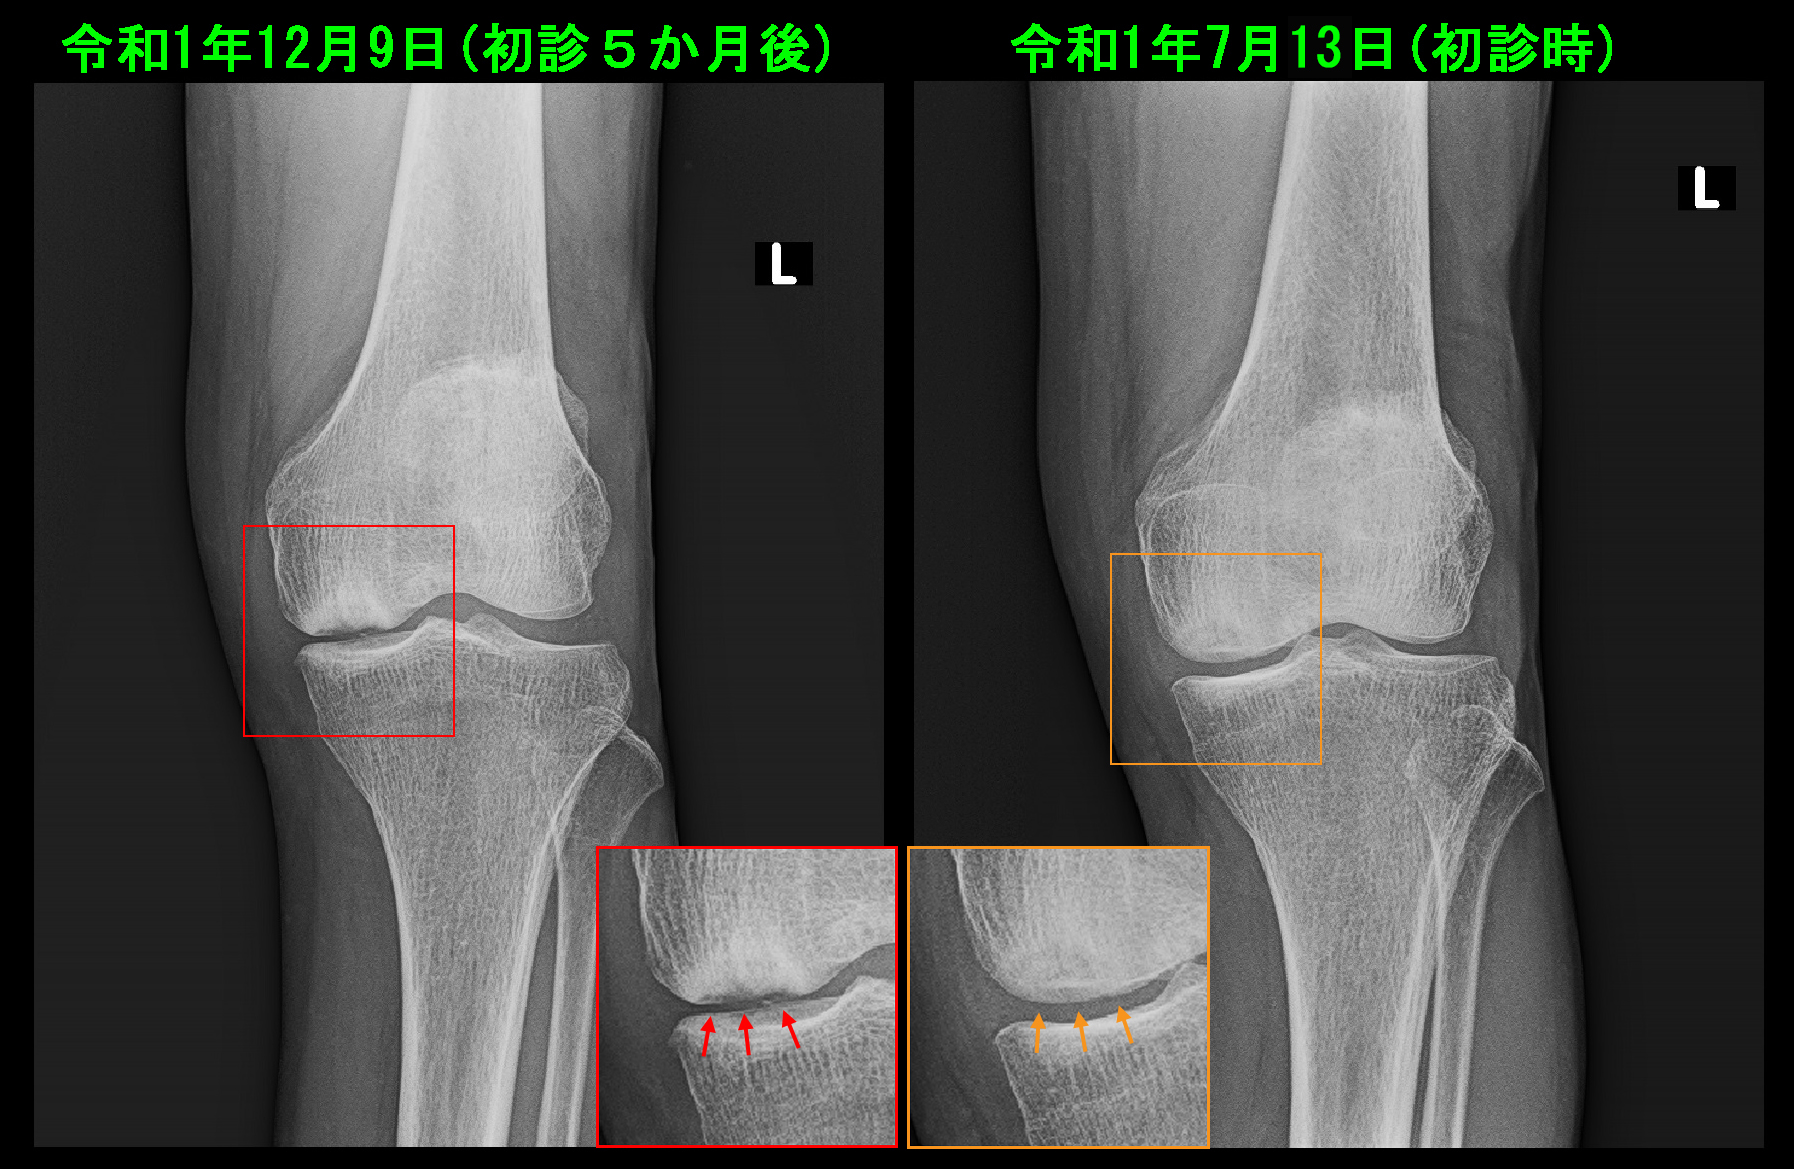

ところが、12月9日に左膝痛が増悪しVAS8となりました。内顆部の骨壊死が陥没したのです。

初診時には連続性がみられた(オレンジ矢印)大腿骨の関節面の骨のラインの連続性が絶たれています。(赤矢印)